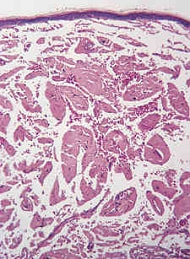

アミロイドーシスは、きわだった症状がなく、診断がむずかしい。疑いのある臓器の細胞をとり生検する

診断の確定には腎生検が必要ですが、体への負担が大きいため、より負担の少ない消化管の粘膜で生検を行うこともあります。ここでアミロイドの沈着が認められれば、腎臓にも沈着していることが予測されるためです。

診断のためには、胃もしくは大腸の内視鏡下粘膜生検を行い、アミロイドの沈着を確認します。